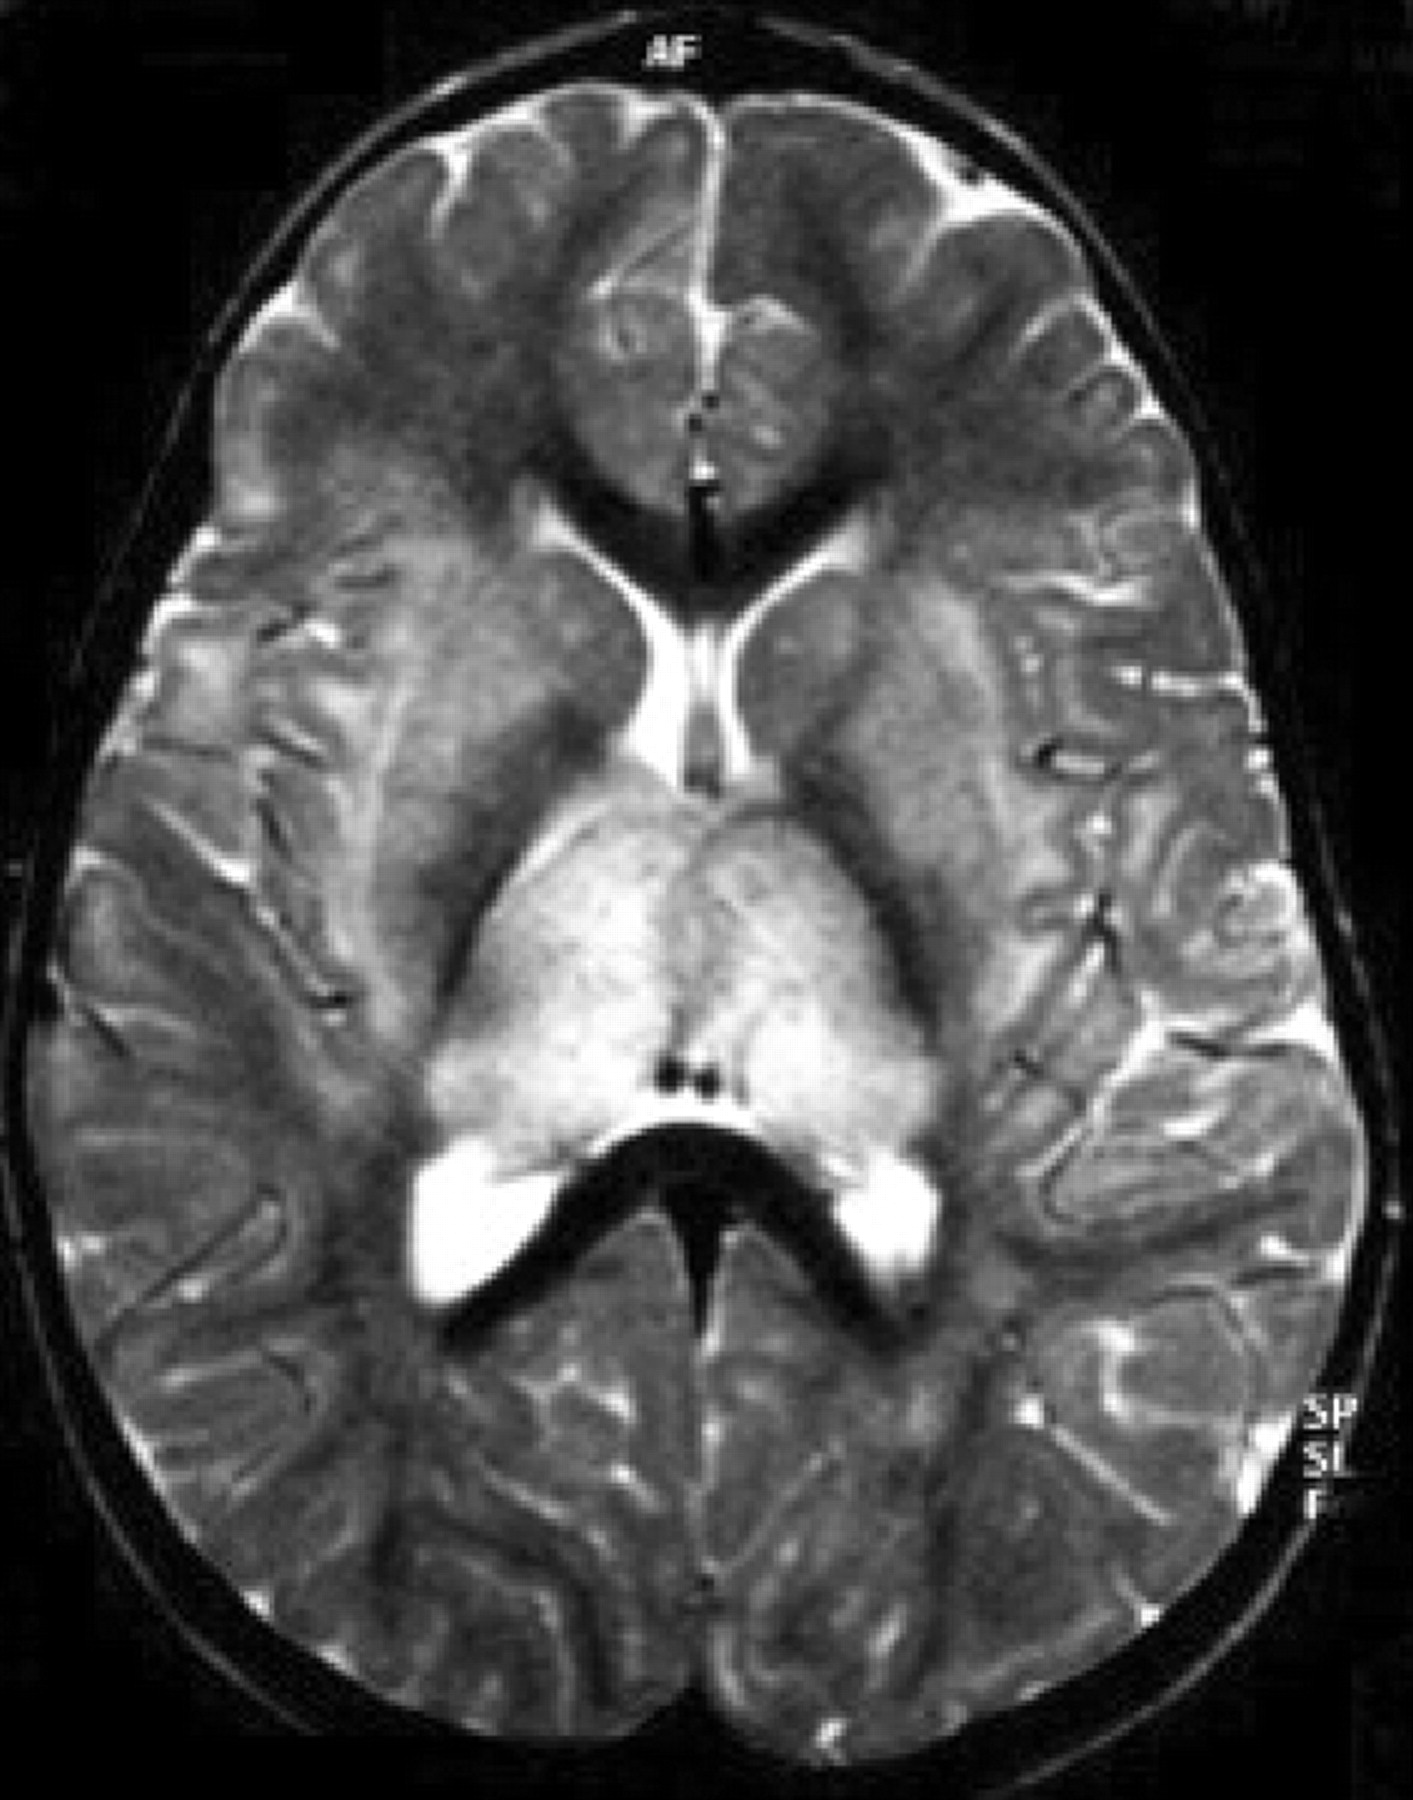

神经影像学在建立ADEM的诊断是非常重要的。在t2加权MRI异常最常见的确定和fluid-attenuated反转恢复序列(天赋)是不完整的,不加边的区域信号强度增加。病变ADEM通常大,多个,和不对称。他们通常涉及到皮层下和中央白质和皮质灰白色结两脑半球,小脑、脑干和脊髓。30.花托和基底神经节的灰质经常参与,通常在一个对称的模式。21日,31日室周的白质也经常参与,被描述为30 - 60%的病例。20日,22日,30岁胼胝体病变局限于不太常见。然而,大型邻近白质脱髓鞘病变可能延伸到胼胝体和交叉侧半球。

提出了四种模式的大脑参与描述ADEM的磁共振成像结果21:1)ADEM小病变(少于5毫米;图1);2)ADEM大支流,块状病变,簇状或频繁广泛perilesional水肿和质量效应(图2);3)ADEM附加对称bithalamic参与(图3);和4)急性出血性脑脊髓炎(咳咳),当一些出血的证据可以确定大脱髓鞘病变(图4)。核磁共振成像模式似乎并不与任何特定的结果或残疾,作为大型儿童群体中观察到,21因为大多数病变往往解决后续成像研究。21日,32然而,这种分类可能是有用的在考虑的鉴别诊断ADEM和可能有助于识别那些孩子来说,初始ADEM-phenotype真的是第一个女士的表现。